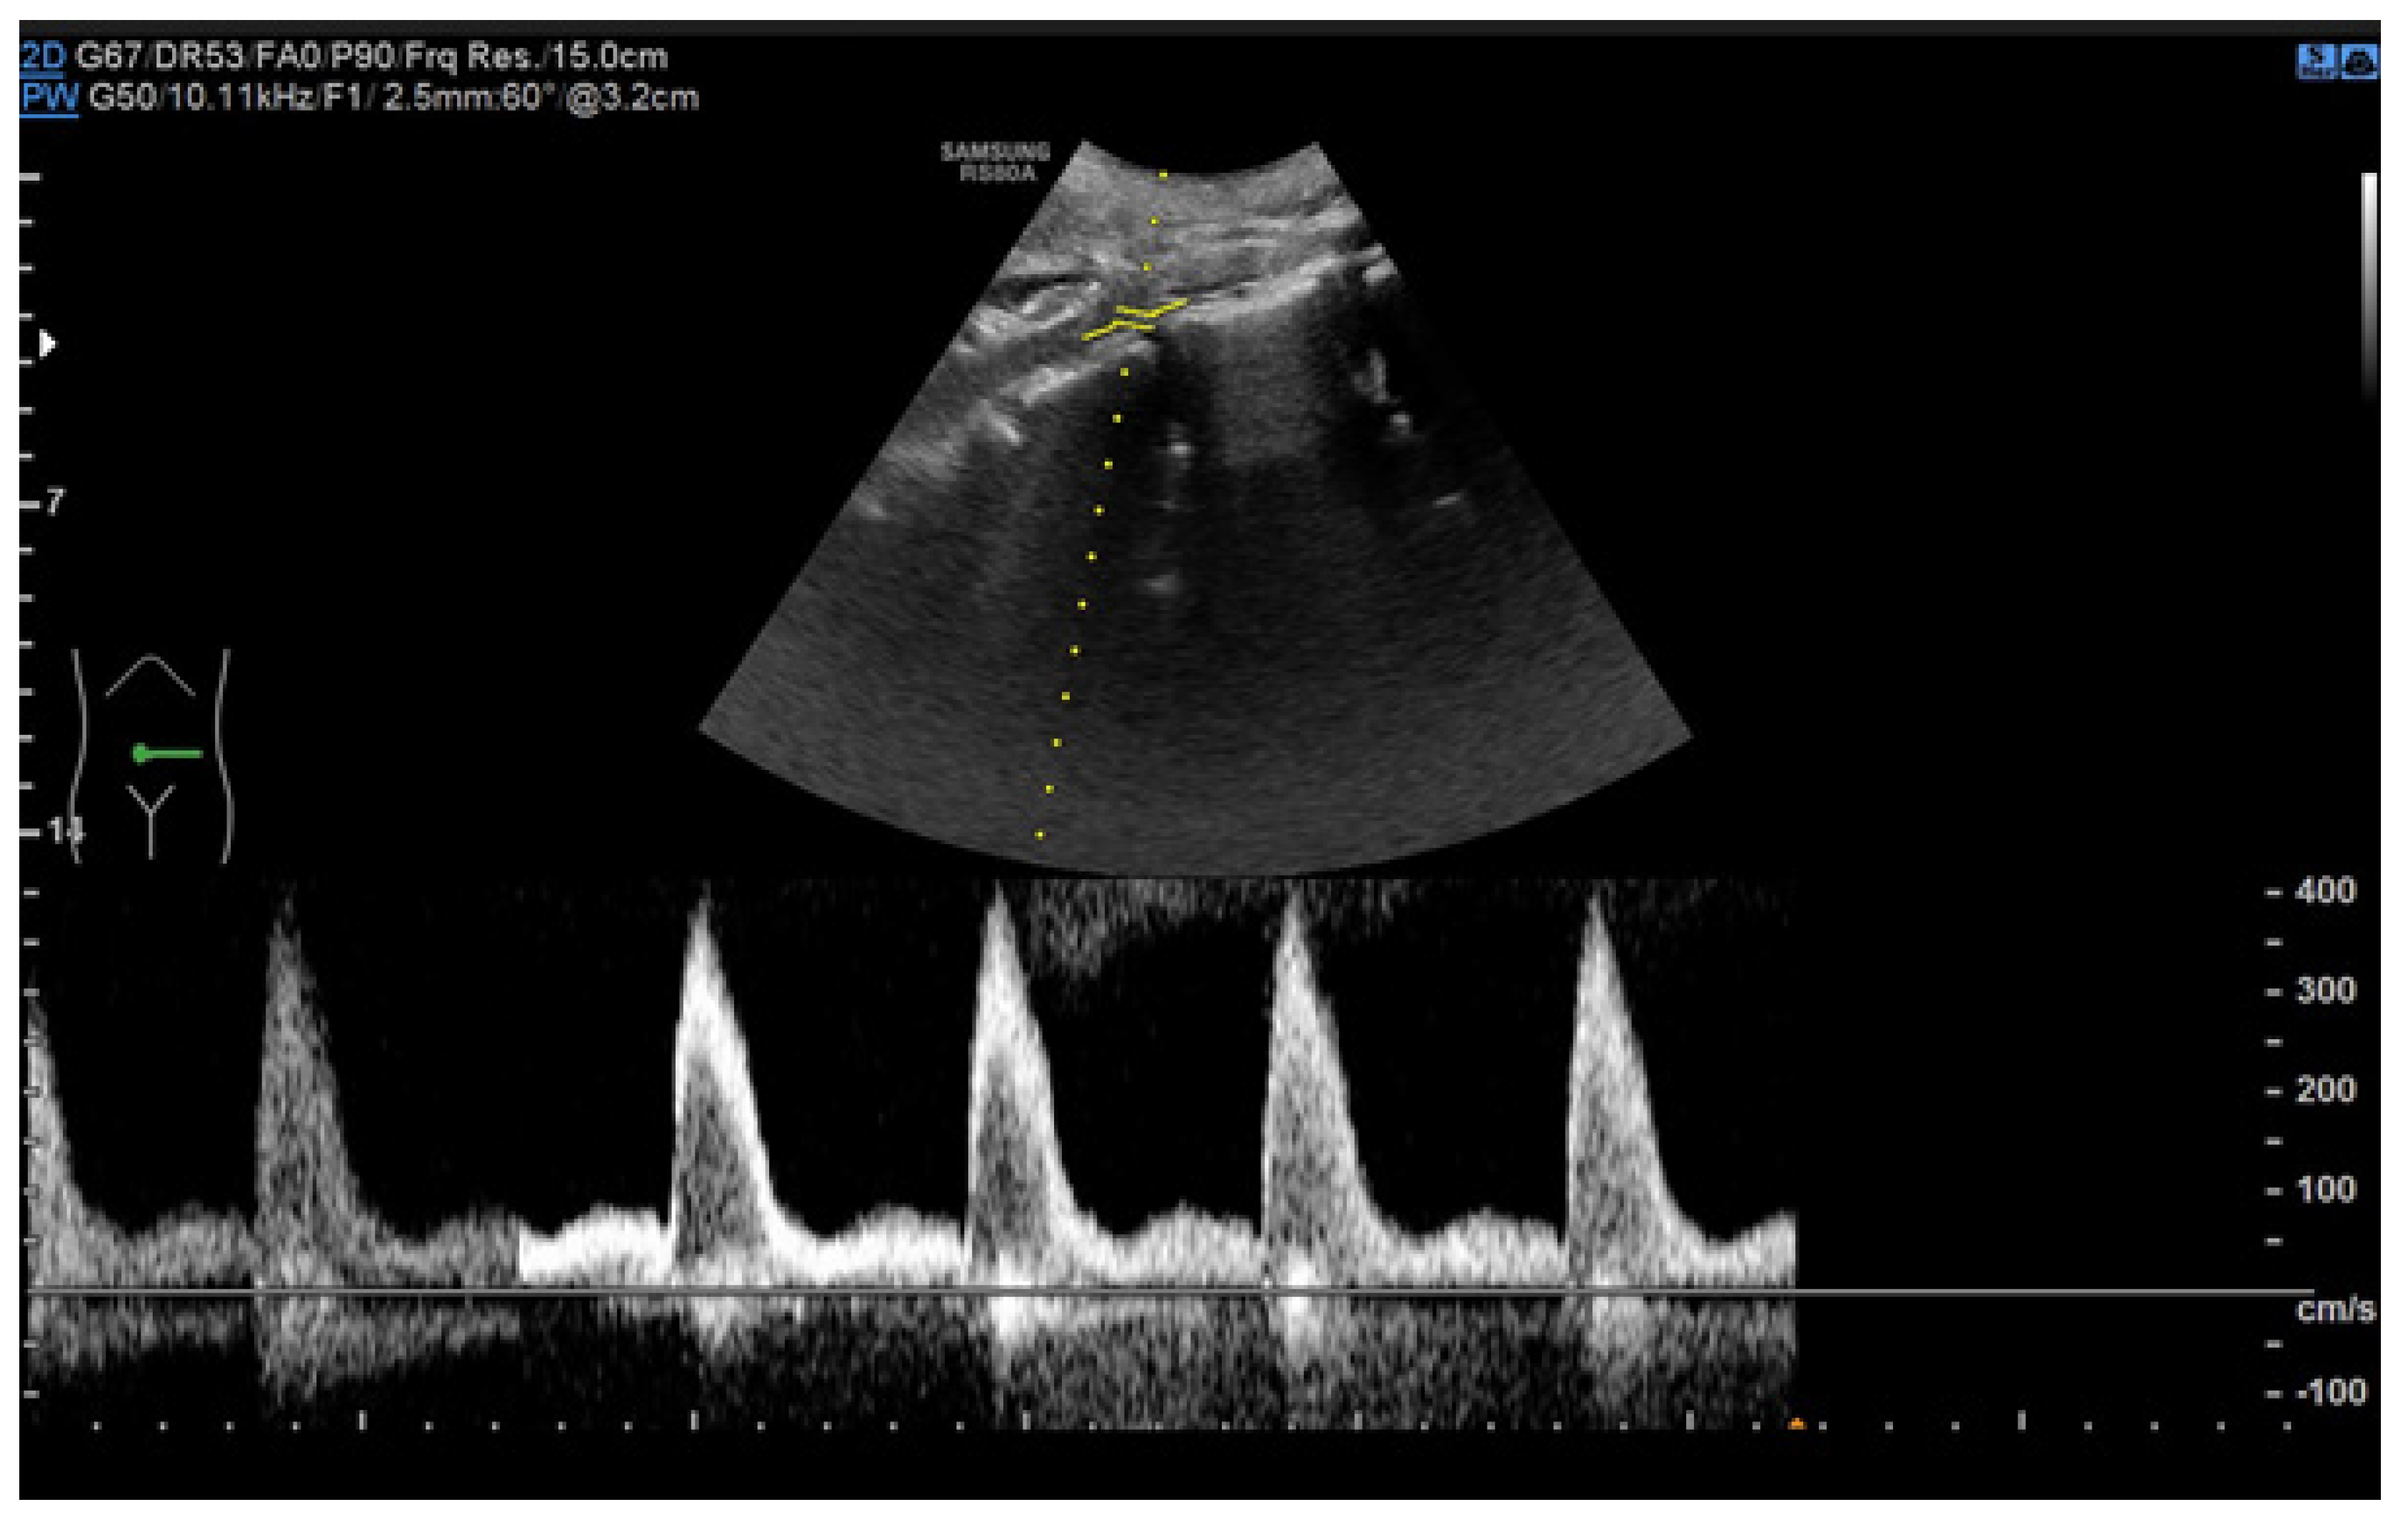

6.1. Ultrasound

- Drelich-Zbroja, A. Polish Society of Ultrasonography Standards—Update: Ultrasound Examination of Renal Arteries. J. Ultrason. 2014, 14, 297–305. [Google Scholar] [CrossRef]

- Stryczyński, Ł. Doppler ultrasound of renal arteries. Arter. Hypertens. Pract. 2022, 8, 186–199. [Google Scholar]

- Saida, K.; Kamei, K.; Hamada, R.; Yoshikawa, T.; Kano, Y.; Nagata, H.; Sato, M.; Ogura, M.; Harada, R.; Hataya, H.; et al. A simple, refined approach to diagnosing renovascular hypertension in children: A 10-year study. Pediatr. Int. 2020, 62, 937–943. [Google Scholar] [CrossRef]

| Normal Value | Parameter |

|---|---|

| 100 cm/s * | PSV (peak systolic velocity) in artery trunk |

| 0.8–1.0 | RAR (renal aortic ratio) in artery trunk |

| ≤70 ms | AT (acceleration time) in intrarenal branches |

| 0.5–0.8 | RI (resistance index) in intrarenal branches |

| 0.78–1.33 | PI (pulsatility index) in intrarenal branches |

| >3 m/s2 | AI (acceleration index) in intrarenal branches |